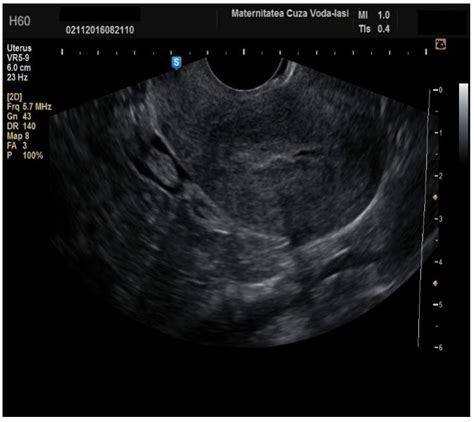

The endometrium is the inner lining of the uterus, which naturally thickens and sheds during a woman's reproductive years. In postmenopausal women, however, this lining should remain thin. When bleeding occurs after menopause, or if there is concern regarding uterine abnormalities, an Endometrial Cancer Ultrasound is typically the first line of defense. This imaging technique uses high-frequency sound waves to create detailed images of the uterus, allowing radiologists and gynecologists to measure the thickness of the endometrium, often referred to as the endometrial stripe.

There are two primary types of ultrasound used to examine the endometrium: transabdominal and transvaginal. For the best visualization of the uterus, the transvaginal approach is generally preferred.

• Transvaginal Ultrasound: A specialized, slim transducer is inserted into the vagina. This provides much higher resolution images, particularly of the endometrium, because the transducer is positioned closer to the uterus.

While an Endometrial Cancer Ultrasound is highly effective, it has limitations that patients and providers must understand. Firstly, it is a morphological assessment; it looks at structure, not cellular function. Therefore, it cannot differentiate between benign hyperplasia (an overgrowth of cells), polyps, or malignant cells.

Secondly, visualization can be impaired in certain patients. Factors such as uterine position (e.g., a retroverted uterus), obesity, or large fibroids can make it challenging to obtain a clear, accurate measurement of the endometrial stripe. In these instances, the physician may recommend alternative imaging, such as magnetic resonance imaging (MRI), or proceed directly to an endometrial biopsy to ensure an accurate diagnosis.